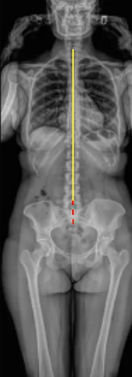

Full Length Spine

Coronal Balance

Apical Vertebral Translation (AVT)